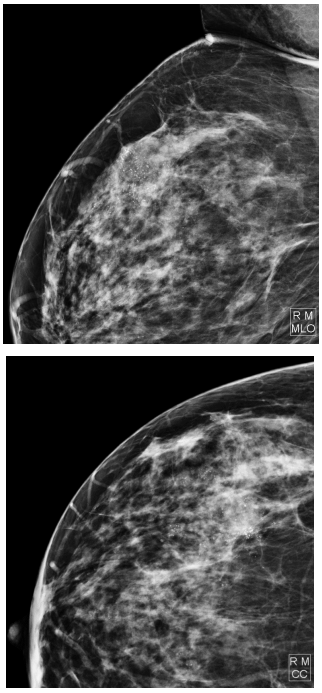

RMC, 58 anos, assintomática, comparece a unidade com

resultado de mamografia de screening realizada há cerca

de 3 meses. Relata que exames não possuem laudos pois

os perdeu em uma enchente. Considerando as imagens,

assinale a conduta mais adequada: